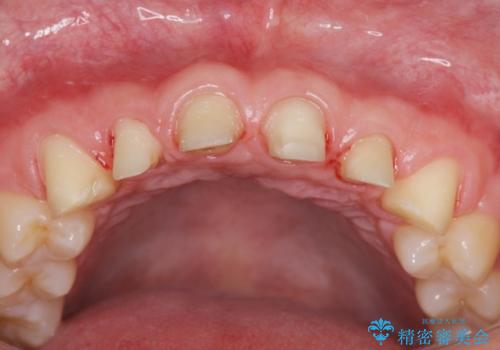

歯周外科を行い、歯ぐきの状態を整えた前歯セラミック治療

- 「前歯の見た目、歯ぐきの腫れを改善したい。」と希望され来院されました。

前歯には接着性の維持装置や、中途半端な形の連結クラウンが装着され、清掃性が悪く歯ぐきの腫れや、歯ぐきの形態の不揃いが認められました。

ただ、白いオールセラミッククラウンを製作・装着するのではなく、将来にわたり安定した状況を獲得するため、歯周外科を行い歯ぐきと周囲の歯槽骨の形態を整えていきます。